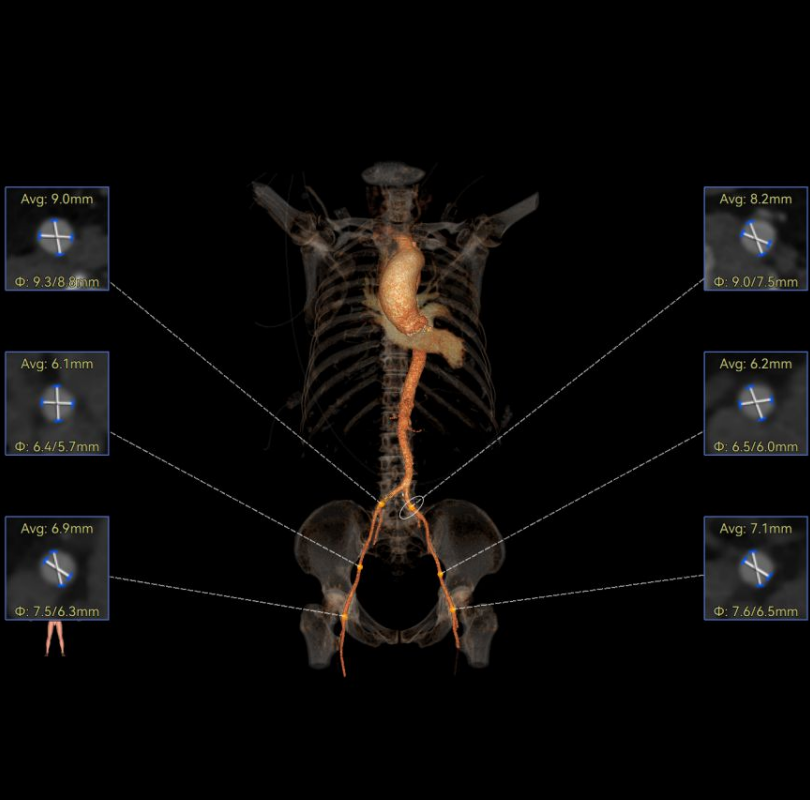

术前CT

Type1型(L-R)二叶瓣,瓣环径27.6mm,LVOT27.2mm,瓣上限制逐渐加重,火山口预估大小24mm,瓣上限制重;双侧冠脉开口高度可,瓣叶不长、窦部空间较大,无冠脉风险;重度钙化,钙化集中在无窦基底部及瓣叶边缘与L-R交界处,心脏角度59.8°;心腔内径可,心室壁无明显增厚,室间隔膜部较短,有一定PPI风险;外周入路无钙化、双侧入路无明显迂曲,左右股动脉内径可、中分叉,主动脉弓处有缩窄,弓距较短,过弓有一定难度。